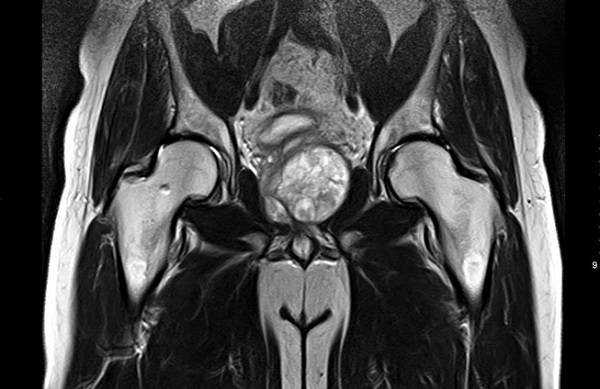

МРТ-признаки остеомиелита лонных костей: расширение сочленения и скопление жидкости с формированием параартикулярных затеков (длинные стрелки), разрастание грануляционной ткани (короткие стрелки), Т2-ВИ, аксиальная (а) и коронарная (в) плоскости